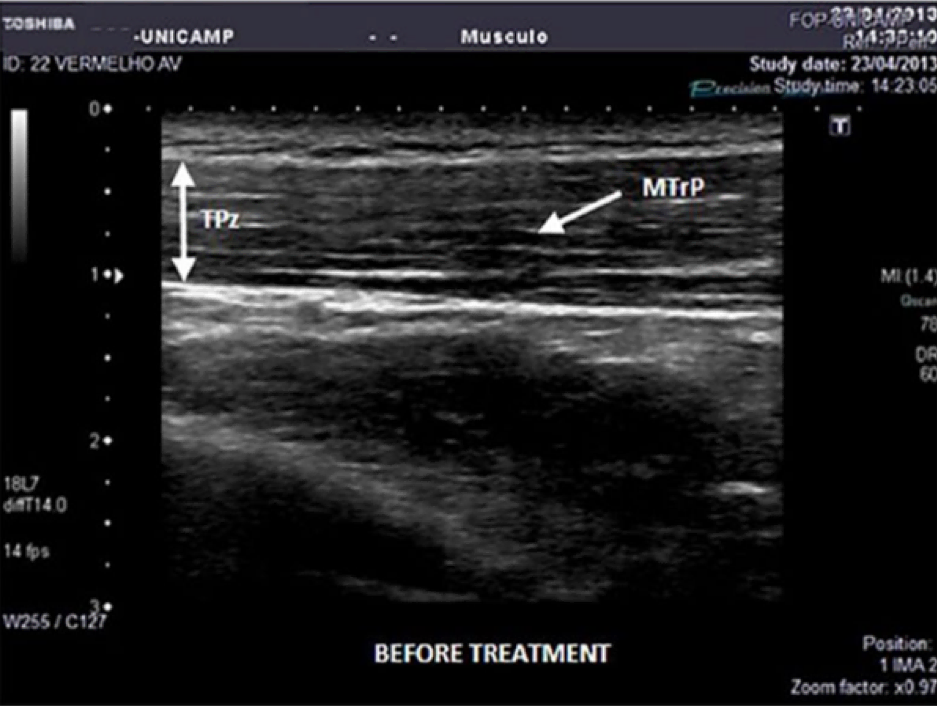

An educational session was provided for the raters. It included the characteristics of the MTrP as described in the literature. Ultrasound of the upper trapezius with independent blinded analysis by two inexperienced and one experienced rater. Each rater examined each US image twice.

For the detection of a myofascial trigger point: Inexperienced intra-rater Cohen’s kappa were 0.28 to 0.49, inter-rater were -0.13 to 0.18. Experienced intra-rater Cohen’s kappa 0.69.

Inexperienced raters demonstrated poor intra- and inter- rater reliability. Good intra-rater reliability was found in the experienced examiner. If ultrasound is used for the diagnosis of MTrP then it is essential that the clinician receive the appropriate training.